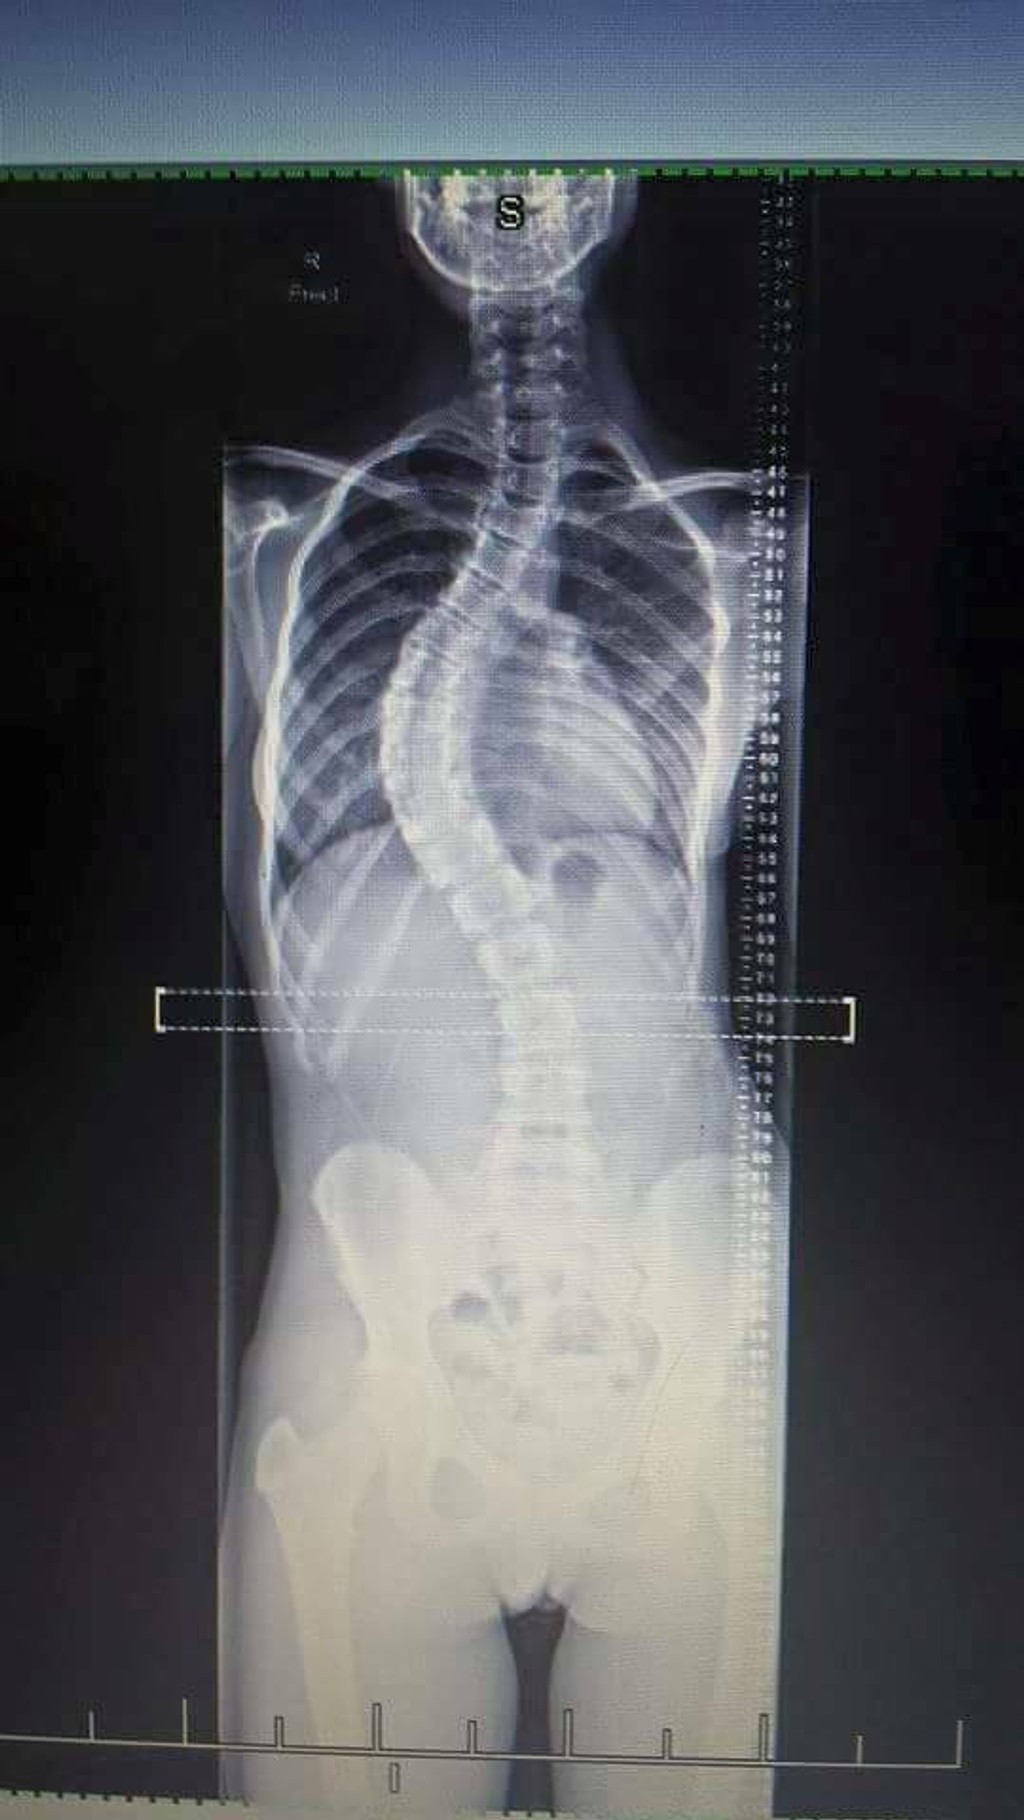

Dievča trpí vzácnou chorobou. Chrbticu mala o 55 stupňov vykrivenú

Sam Hansen a jej chrbtica predtým a teraz.

Mladá Novozélanďanka Sam Hansen má vzácnu chorobu. Ide o idiopatickú skoliózu. Chrbticu mala vykrivenú o 55 stupňov. Prvýkrát si to všimla, keď mala dvanásť rokov a chcela sa zohnúť pre niečo na zemi. Rodičia si všimli, že jej zvláštne trčia rebrá. Začala nosiť veľké a rozťahané veci, aby to zakryla.

Sam podstúpila operáciu, po ktorej má v tele sedemnásť skrutiek a dve železné tyče. Ako píše mirror.co.uk, narástla po nej o desať centimetrov. Chrbtica sa jej o dosť narovnala, teraz ju má vykrivenú len o 20 stupňov, čo je už prijateľné. Jej zdravotný stav sa zlepšuje a už začala aj športovať.